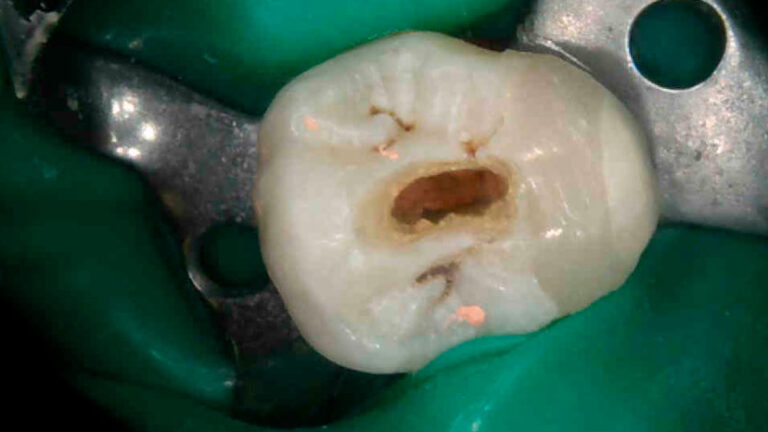

El doctor Noé Hernández nos presenta en este caso clínico una apertura de tipo conservador en un diente…